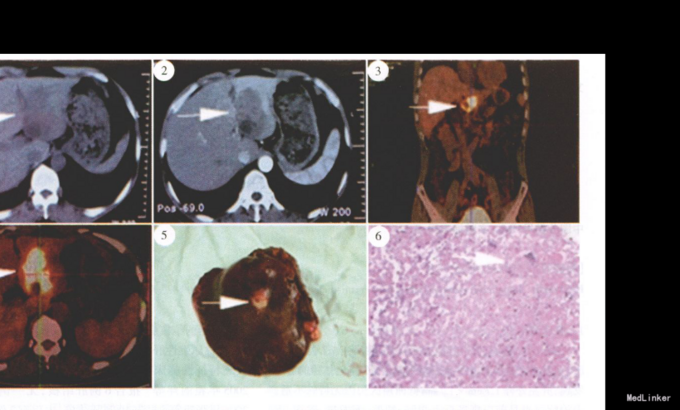

查体:一般情况尚可,全身皮肤黏膜未见黄染,浅表淋巴结未触及,心肺未及异常。腹平软,剑突下压痛,未及包块。 辅查:肿瘤标记物甲胎蛋白(AFP)、CA19-9、癌胚抗原(CEA),血常规、生化均正常。胸片提示未见异常。B超:肝左外叶1.7 cm×1.7 cm 低回声区;上腹部CT 平扫+增强结果:“肝左叶占位性病变,考虑:(1)肝左叶癌,其内部分坏死;(2)肝左叶胆管细胞癌,并邻近肝 内胆管扩张”(图1、2)。PET-CT 报告:“肝左外叶占位性病变,代谢活跃,考虑原发性肝癌”(图3、4)。

考虑诊断:肝左叶占位性病变:(1)肝内胆管癌;(2)原发性肝癌。 予手术治疗,术中见肝左外叶探及肿瘤约7.0 cm×6.0 cm×6.0 cm,质硬,边界尚清(图5),肝脏脏面可见3.0 cm×3.0 cm 肿块组织突出肝实质,表面光整;肠管未及特殊病变。术中诊断:肝内胆管癌(肝左外叶),手术行肝左外叶切除+肝门淋巴结清扫。术后本院病理结果:大体标本剖面为实性结节肿物,黄褐色,质地脆;光镜可见干酪样坏死、Langhans 巨细胞、上皮样细胞以及淋巴细胞浸润(图6)。病理诊断:(肝左外叶)符合肝结核病理改变;No.12a 和No.12p 淋巴结示慢性炎;外院会诊病理切片示:(肝左外叶)肝肉芽肿性炎伴坏死,片内提示结核(图6)。术后查血沉39 mm/h,抗结核抗体阴性,结核菌素试验阴性。 修正诊断:肝结核